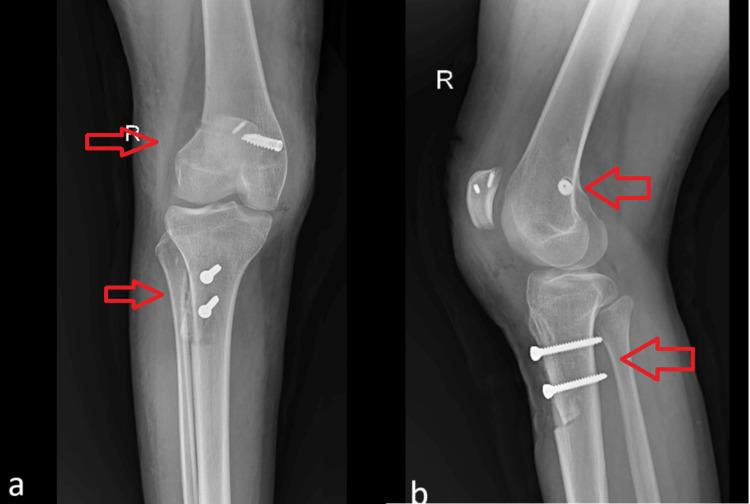

This case report details the clinical evaluation, imaging findings, and surgical management of a 17-year-old female with a two-year history of persistent knee pain and recurrent patellar dislocations. Despite the absence of traumatic injury, the patient exhibited significant anatomical abnormalities, including a laterally dislocated patella, shallow trochlear groove, increased tibial tuberosity to trochlear groove (TT-TG) distance, and patella alta by calculating Insall-Salvati ratio. The Insall-Salvati ratio is a radiographic measurement used to assess the position of the patella within the knee joint. It is calculated by dividing the length of the patellar tendon (from the lower pole of the patella to its insertion on the tibial tubercle) by the length of the patella itself (from its superior to inferior pole). This ratio is commonly used in the evaluation of patellar tracking disorders and patellar instability. Typically, a ratio greater than 1.2 is considered indicative of patella alta (high-riding patella), while a ratio less than 0.8 suggests patella baja (low-riding patella). The surgical intervention involved a tibial tuberosity osteotomy (TTO), distalization, and medial patellofemoral ligament (MPFL) reconstruction using the gracilis tendon, resulting in successful realignment as confirmed by postoperative imaging. A postoperative rehabilitation program, including physical therapy and pain management, was initiated to optimize recovery and enhance quadriceps strength and proprioception. This case underscores the importance of a comprehensive surgical approach in addressing recurrent patellar dislocation associated with complex anatomical variations, providing insights into effective management strategies for similar cases.